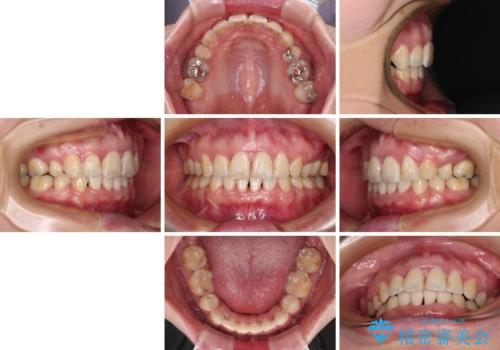

出っ歯による口の閉じにくさを治したい ワイヤー装置を用いた抜歯矯正

- 出っ歯と口の閉じにくさ、デコボコを気にして来院された患者様です。

口元の突出感を改善するため、上下左右第一小臼歯4本の抜歯を行い、ワイヤー装置による矯正治療を行うこととしました。

上下前歯の距離が大きかったため、上下の歯が接触するまでに時間がかかりました。

それでも目安である2年半で終えることができ、患者様には大変満足していただけました。